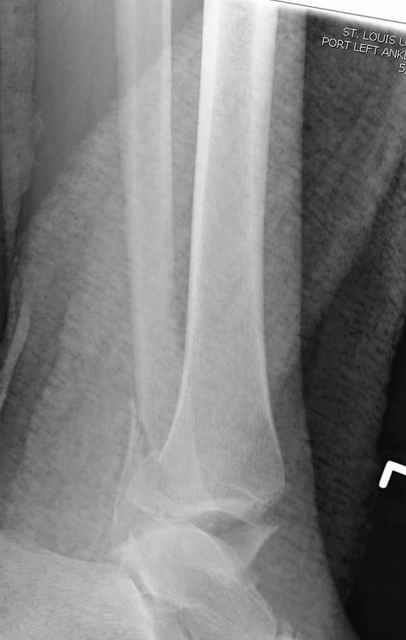

Dear all,40 y.o. man had sustained this terrible fracture falling from a motorbike.

Closed fracture.

This is really Pilon Fx (C3.3; the high energy and the extent of distal tibia comminution are defining it).

This is a pilon fracture. I suggest fixation of the fibula with a one-third tubular plate and a joint spanning external fixator on the medial side as initial treatment. If the tibial articular surface cannot be reconstituted, the patient will require an arthrodesis.